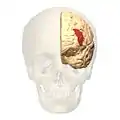

Brodmann area 46

Brodmann area 46, or BA46, is part of the frontal cortex in the human brain. It is between BA10 and BA45.

BA46 is known as middle frontal area 46. In the human brain it occupies approximately the middle third of the middle frontal gyrus and the most rostral portion of the inferior frontal gyrus. Brodmann area 46 roughly corresponds with the dorsolateral prefrontal cortex (DLPFC), although the borders of area 46 are based on cytoarchitecture rather than function. The DLPFC also encompasses part of granular frontal area 9, directly adjacent on the dorsal surface of the cortex.

Lateral view.